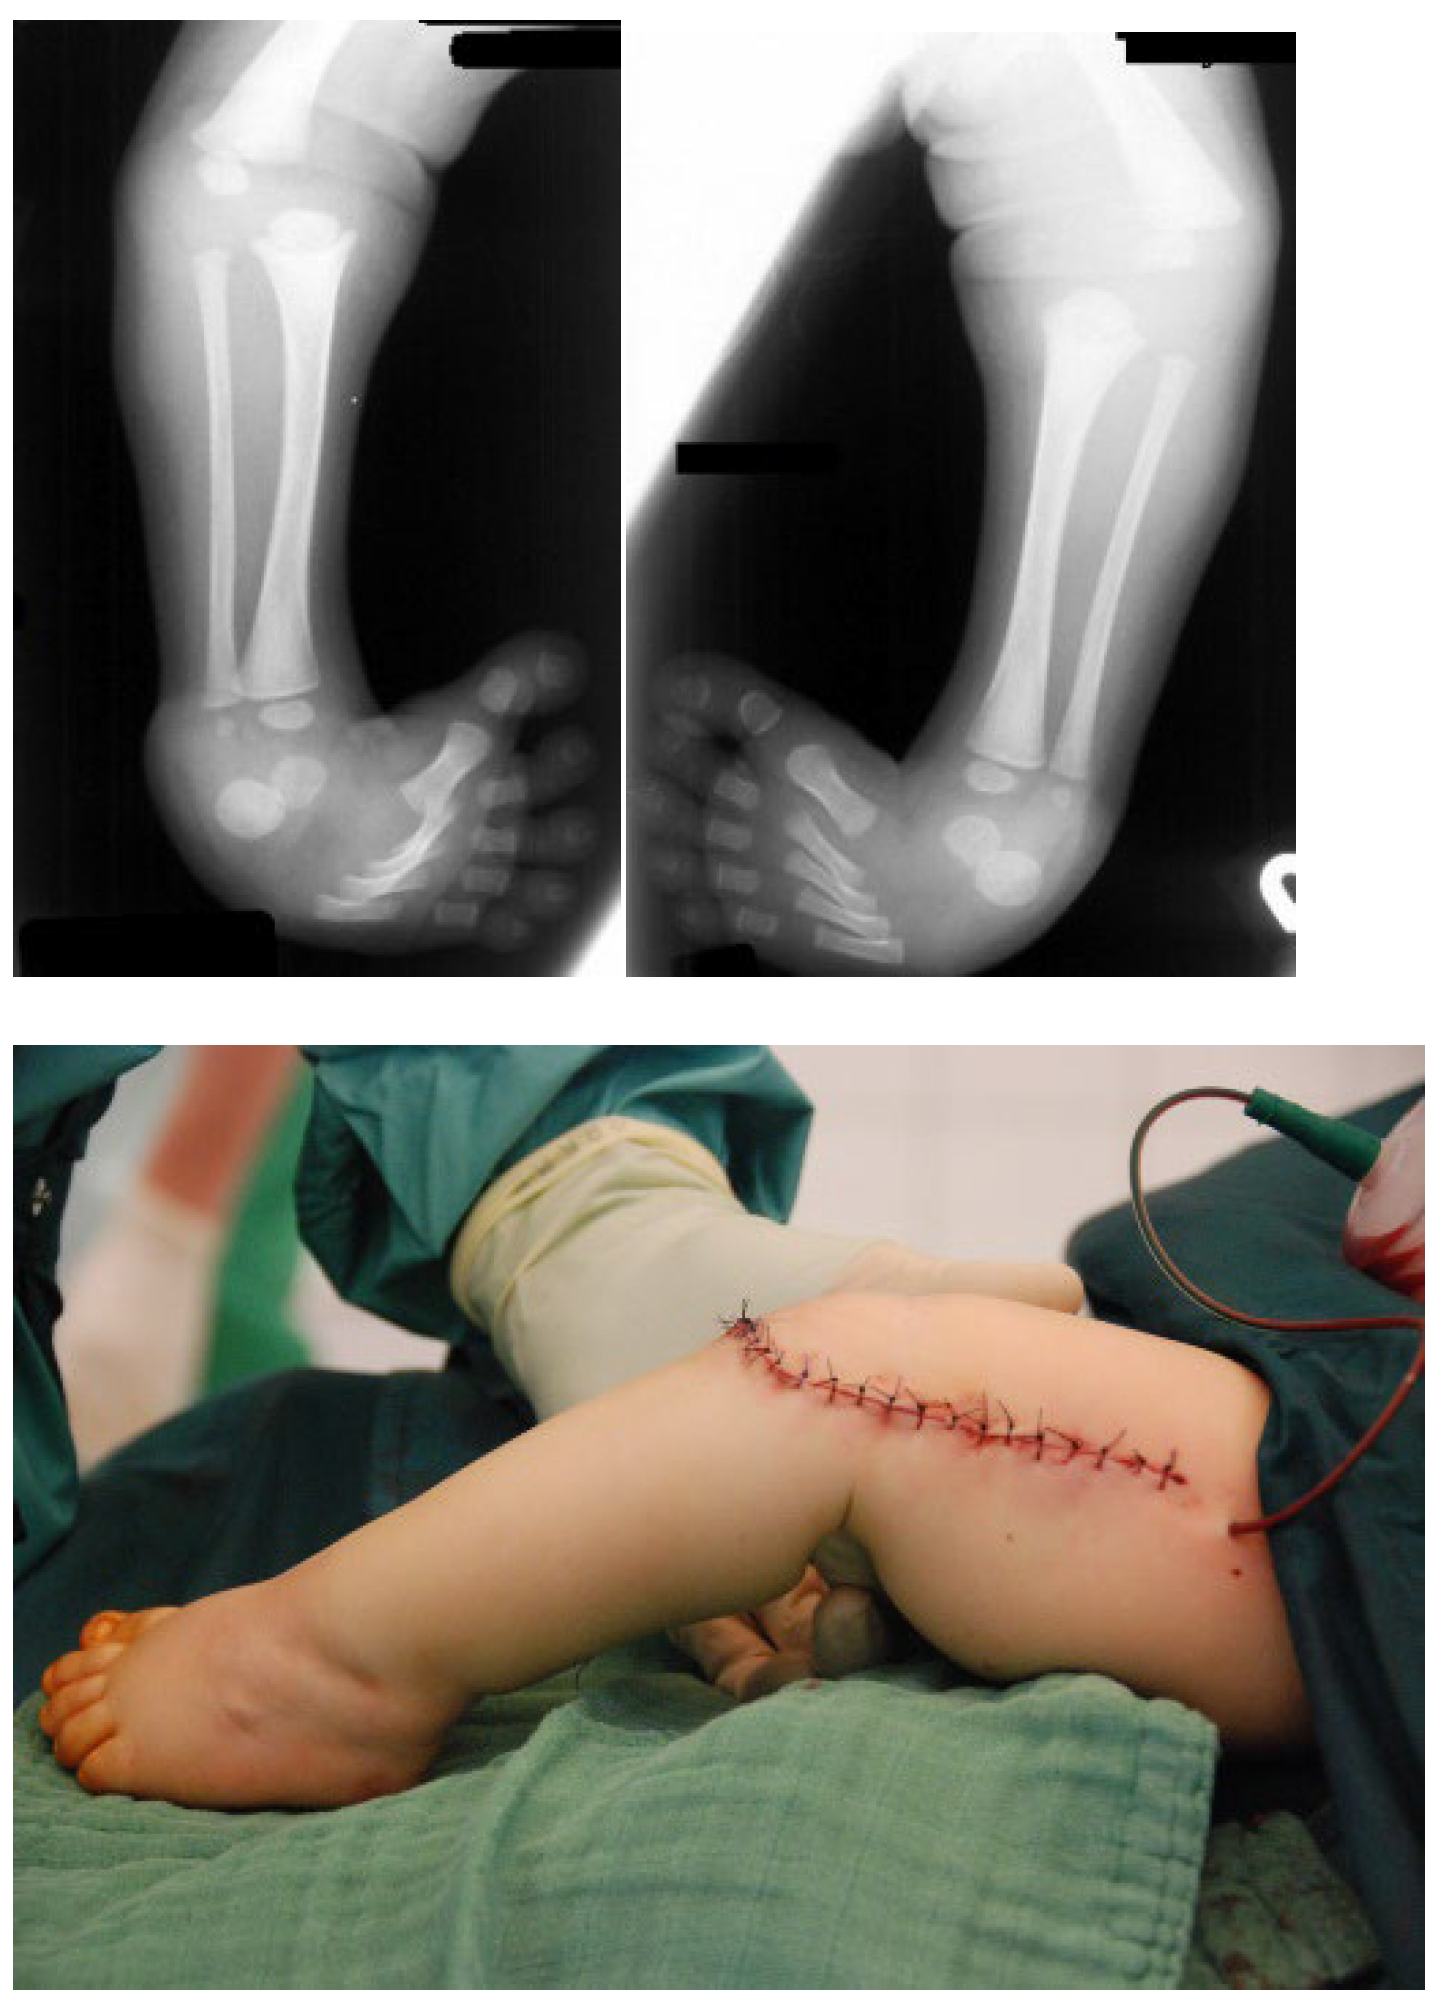

3.4. Surgical Interventions to Correct Hip/Knee Dislocations and Talipes Equinovarus

3.5. Surgical Intervention to Correct Traumatic Tertaplagia